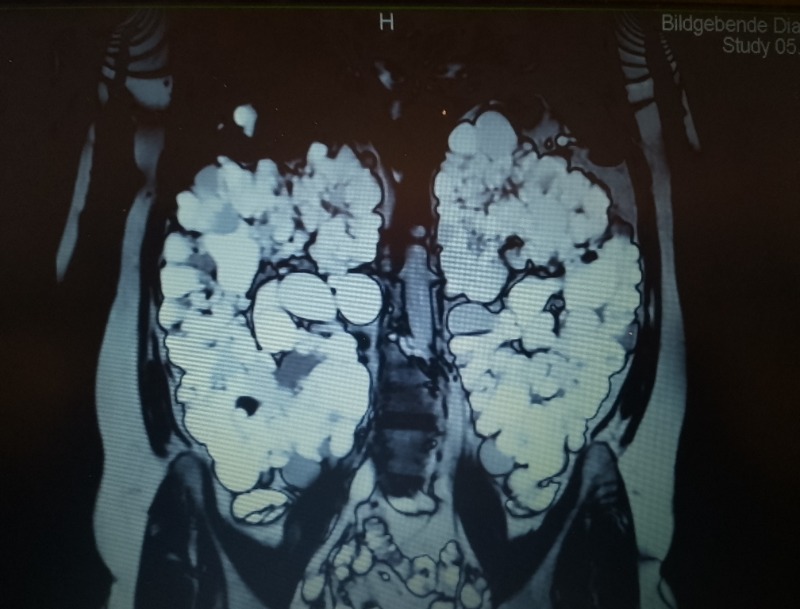

Suche Klink für beidseitige Nephrektomie meiner Zystennieren 20 Feb 2026 17:43 #528997